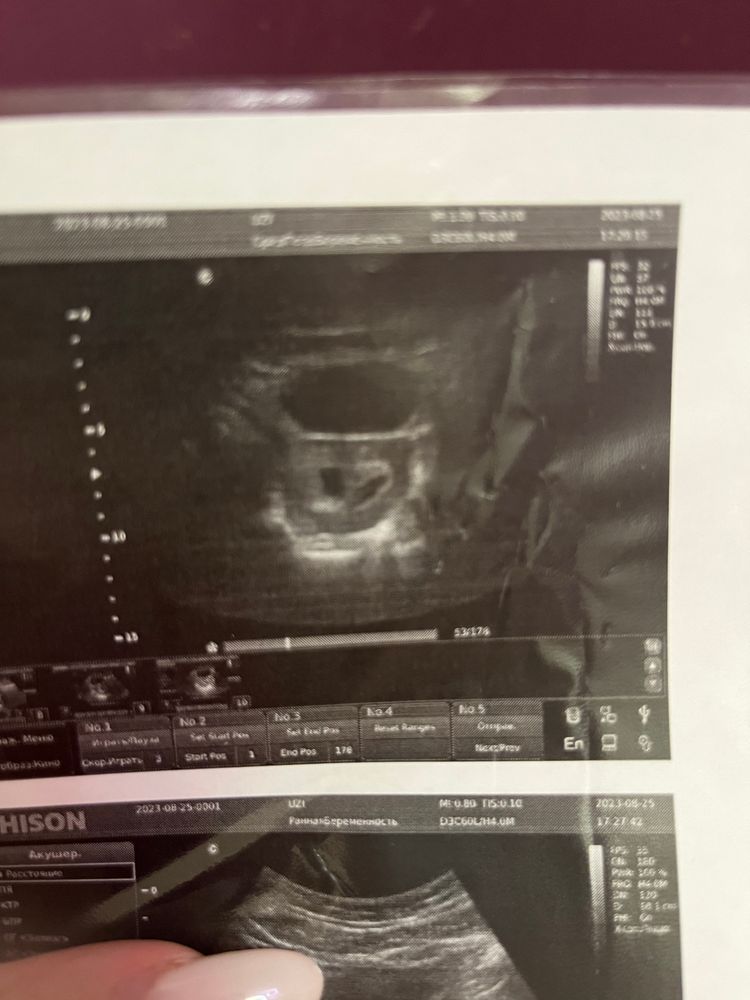

Многоплодная беременностьВсем привет! Что на УЗИ может быть похоже на второе ПЯ? Во вторник на УЗИ было видно одно ПЯ 5мм и вторую непонятную маленькую точку. Ночью пришлось срочно сделать УЗИ. ПЯ выросло до 9мм (есть ЖМ и эмбрион). А рядом поменьше и более овальное что-то очень похожее на ПЯ, которое получается тоже подросло. Врач УЗИ не стал утверждать, что это ПЯ, но и не понятно что тогда. В заключение лишь написал РХГ и размеры, чтобы через 2 недели проверили.

Как у вас было в начале с двойнями? Сразу два ПЯ понятных были или нет?